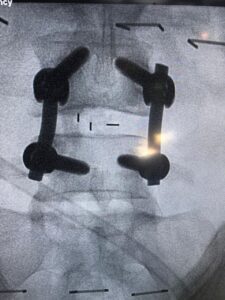

وأضاف د. أبو الراس بأنه تم إجراء العملية الدقيقة بعد موافقة المريضة عليها وعلى الخطة العلاجية ما بعدها، وتمثلت العملية في توسيع القناة العصبية واستئصال الغضروف ووضع دعامة بين الفقرات مع تصحيح الإنزلاق الفقاري وعمل دمج بين الفقرتين الرابعة والخامسة، وتكللت العملية بالنجاح -ولله الحمد- واستطاعت المريضة المشي في أول يوم لها بعد إجراء العملية.